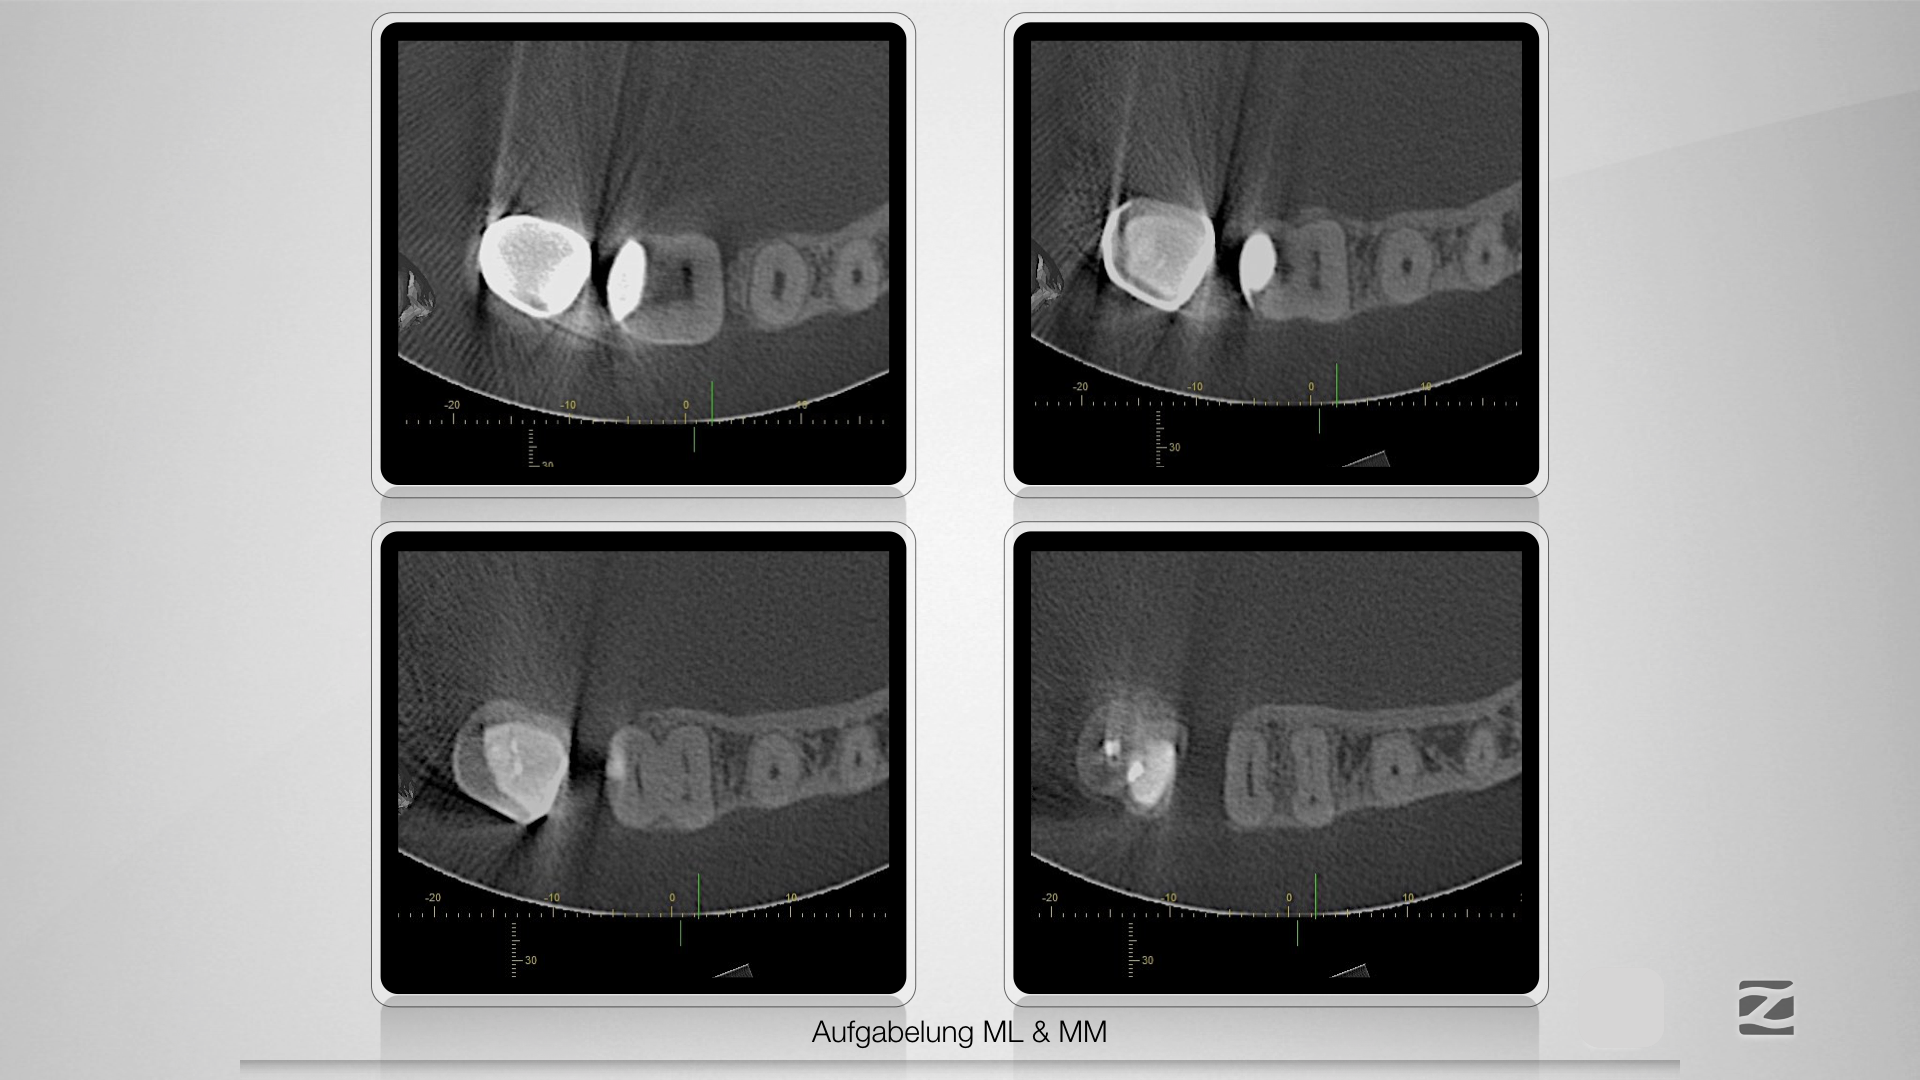

Mit Navigation zum Erfolg